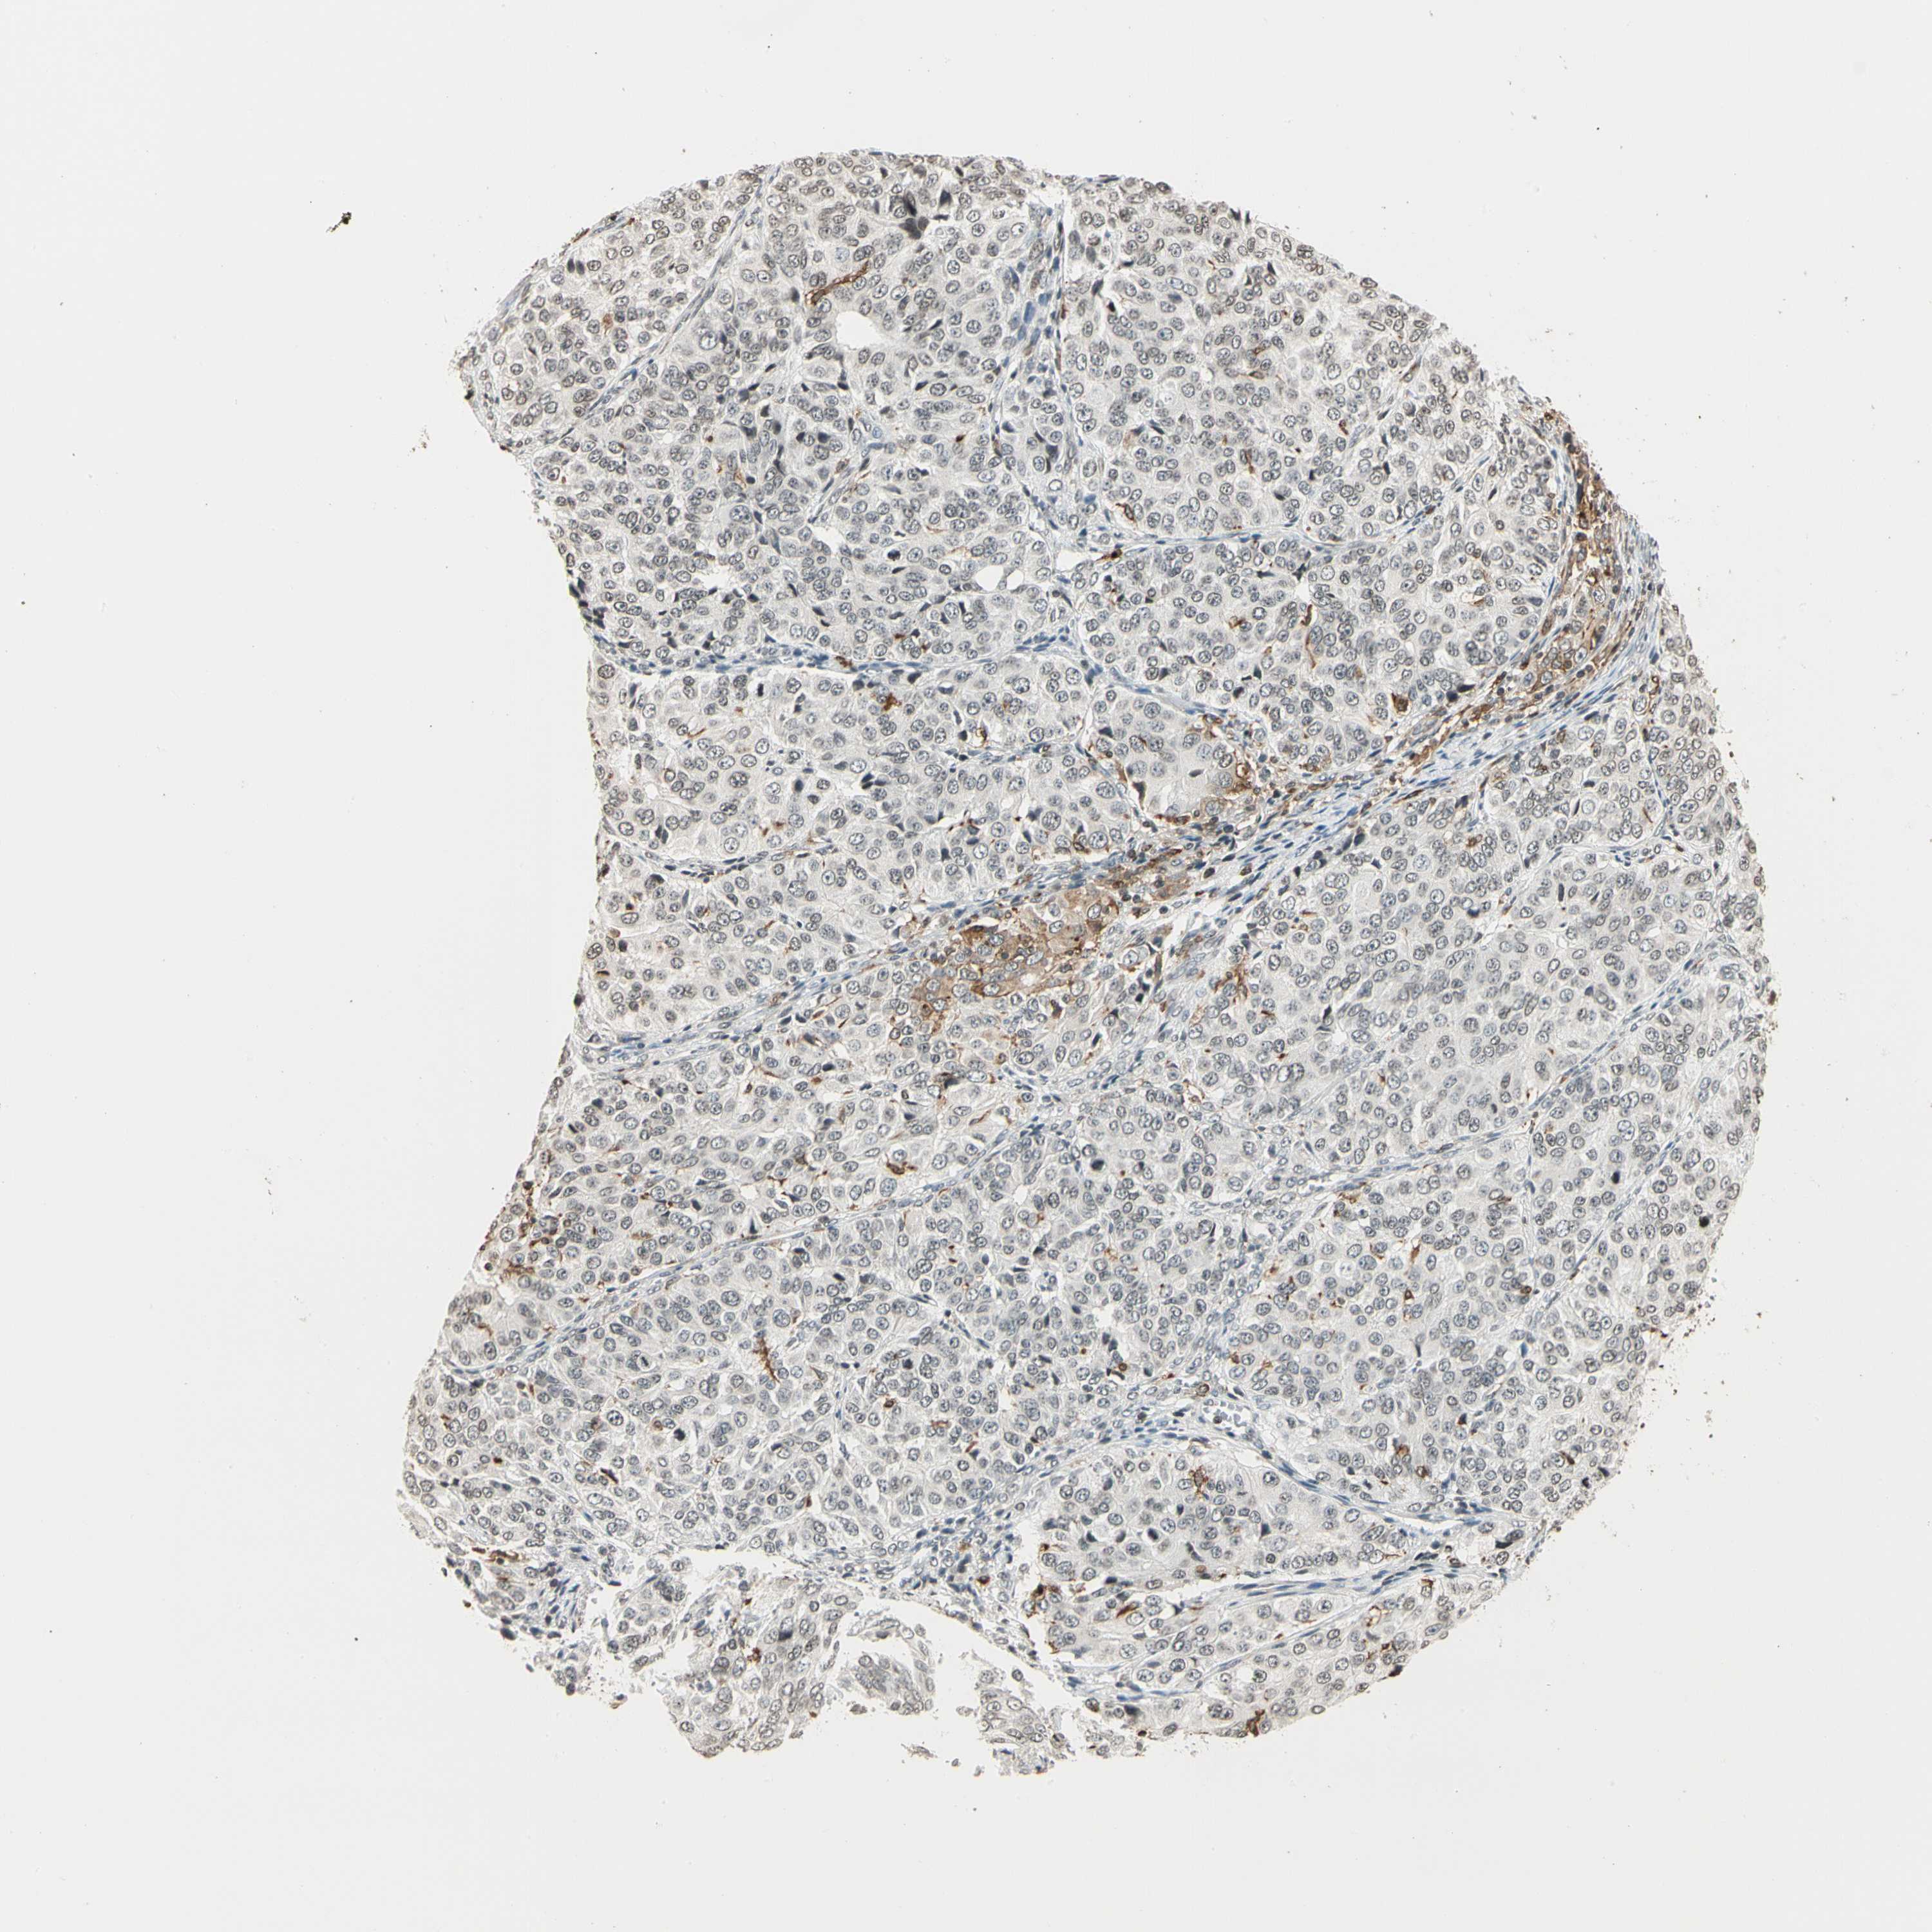

OVARIAN CANCER - Protein expressioni

A mouse-over function shows sample information and annotation data. Click on an image to view it in a full screen mode. Samples can be filtered based on level of antibody staining by selecting one or several of the following categories: high, medium, low and not detected. The assay and annotation is described here.

Note that samples used for immunohistochemistry by the Human Protein Atlas do not correspond to samples in the TCGA dataset.

Antibody stainingi

Antibody staining in the annotated cell types in the current human tissue is reported as not detected, low, medium, or high, based on conventional immunohistochemistry profiling in selected tissues. This score is based on the combination of the staining intensity and fraction of stained cells.

Each image is clickable and will lead to virtual microscopy that enables deeper exploration of all samples and also displays staining intensity scores, fraction scores and subcellular localization as well as patient and tissue information for each sample.

Antibody HPA007641

Antibody CAB022464

Cystadenocarcinoma, serous, NOS

Carcinoma, endometroid

Cystadenocarcinoma, mucinous, NOS

Carcinoma, NOS